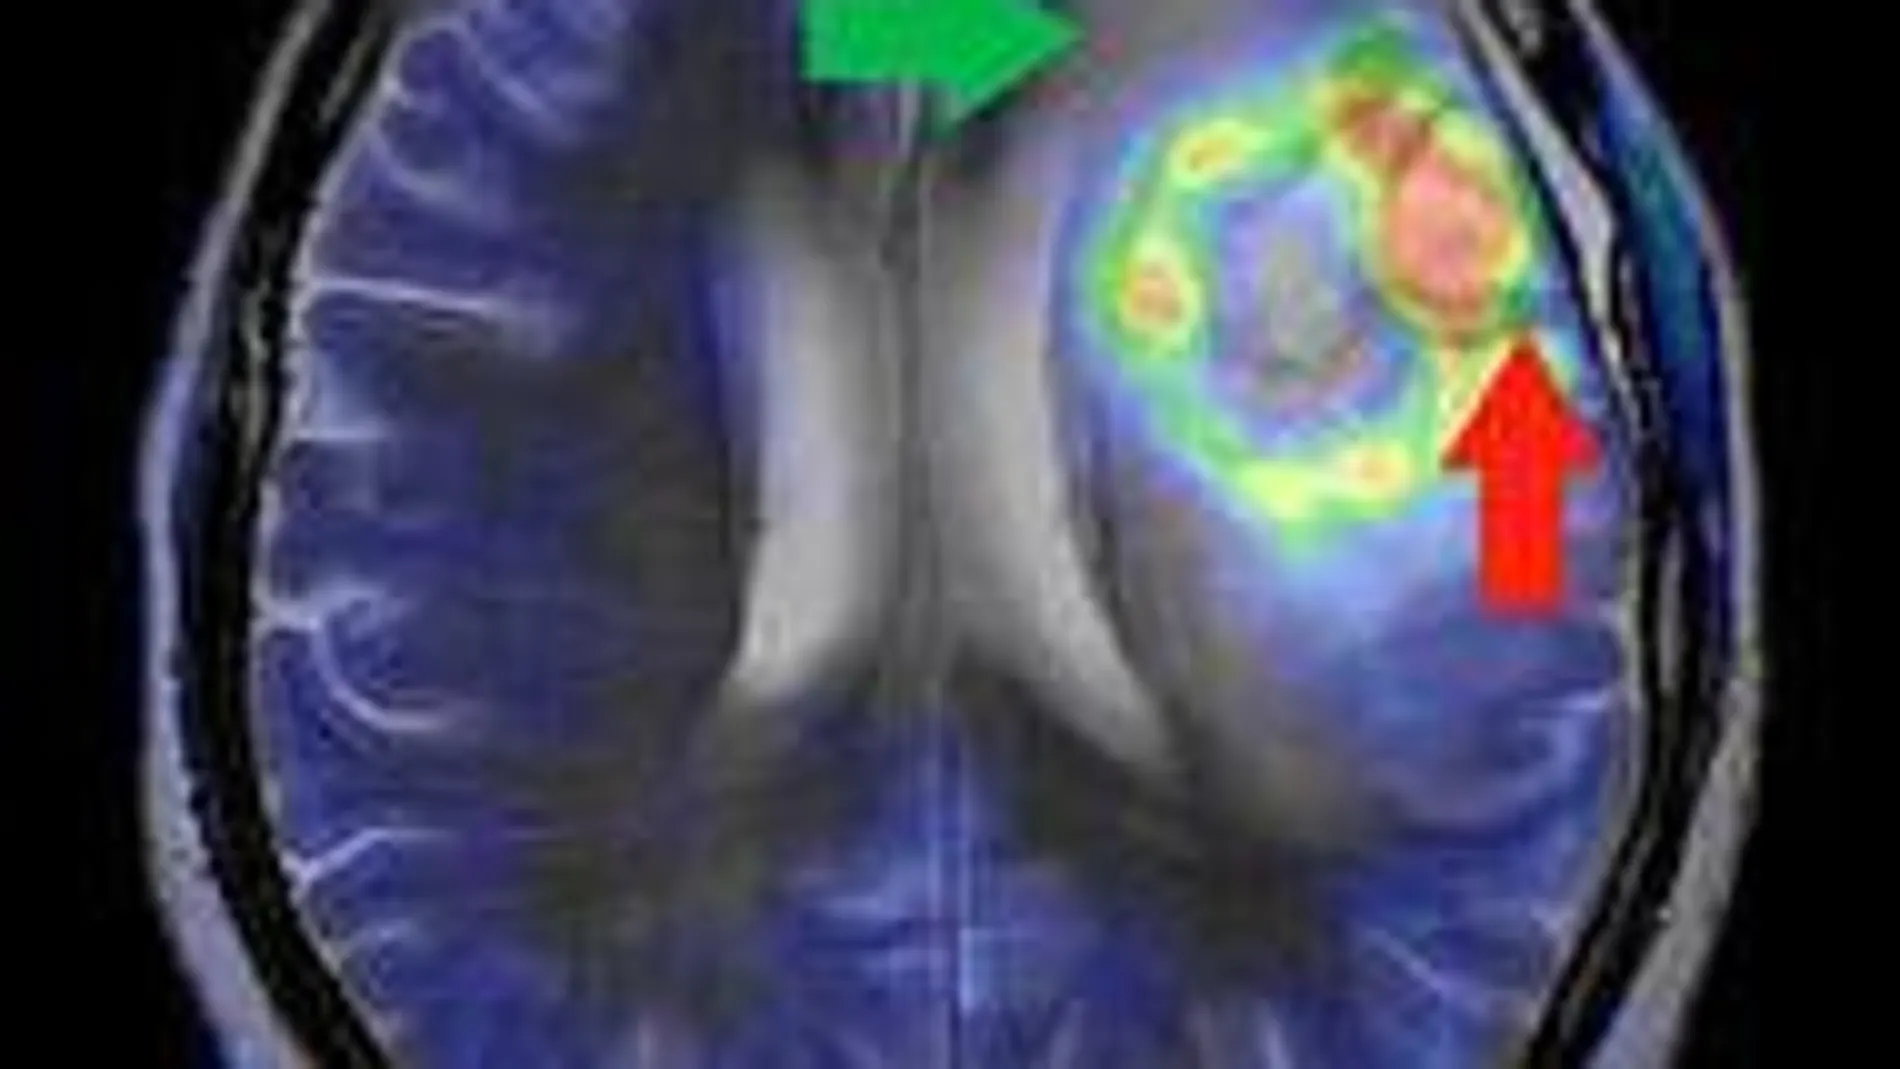

Un algoritmo delimita tumores cerebrales en imágenes médicas

La Asociación Europea de Lógica Difusa y Soft Computing (EUSFLAT) ha premiado un trabajo de investigación del grupo de Inteligencia Artificial de la Universidad Pública de Navarra: El grupo ha desarrollado un algoritmo para mejorar la delimitación de tumores cerebrales en imágenes médicas.

Un trabajo del grupo de Inteligencia Artificial y Razonamiento Aproximado (GIARA) de la Universidad Pública de Navarra, con el que se ha logrado desarrollar un algoritmo para mejorar la delimitación de los tumores cerebrales en imágenes médicas, ha sido premiado por La Asociación Europea de Lógica Difusa y Soft Computing (EUSFLAT).

El trabajo se centra en el estudio de imágenes de cerebros obtenidas a través de resonancia magnética. En concreto, han desarrollado un algoritmo para mejorar el proceso de segmentación de imágenes.

"Mediante la segmentación se separan cada uno de los objetos que forman parte de la imagen. Se analiza cada píxel de manera que todos los que tengan ciertas características en común, se consideran parte del mismo objeto", añade la investigadora.

Jurio también subraya que en el caso de las imágenes médicas, este proceso es fundamental para la delimitación de tumores "donde, si pensamos en zonas como el cerebro, tres milímetros de diferencia pueden marcar la diferencia entre la curación o afectar zonas como el habla o la vista".